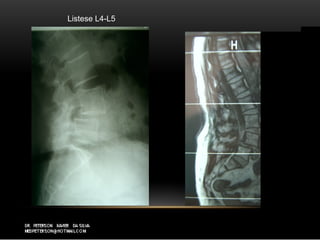

DegenerativaDegenerativa

Listese L4-L5

T1 sagital T2 sagital

degenerativa

T1 sagital T2sagital Listese L4-L5 degenerativa